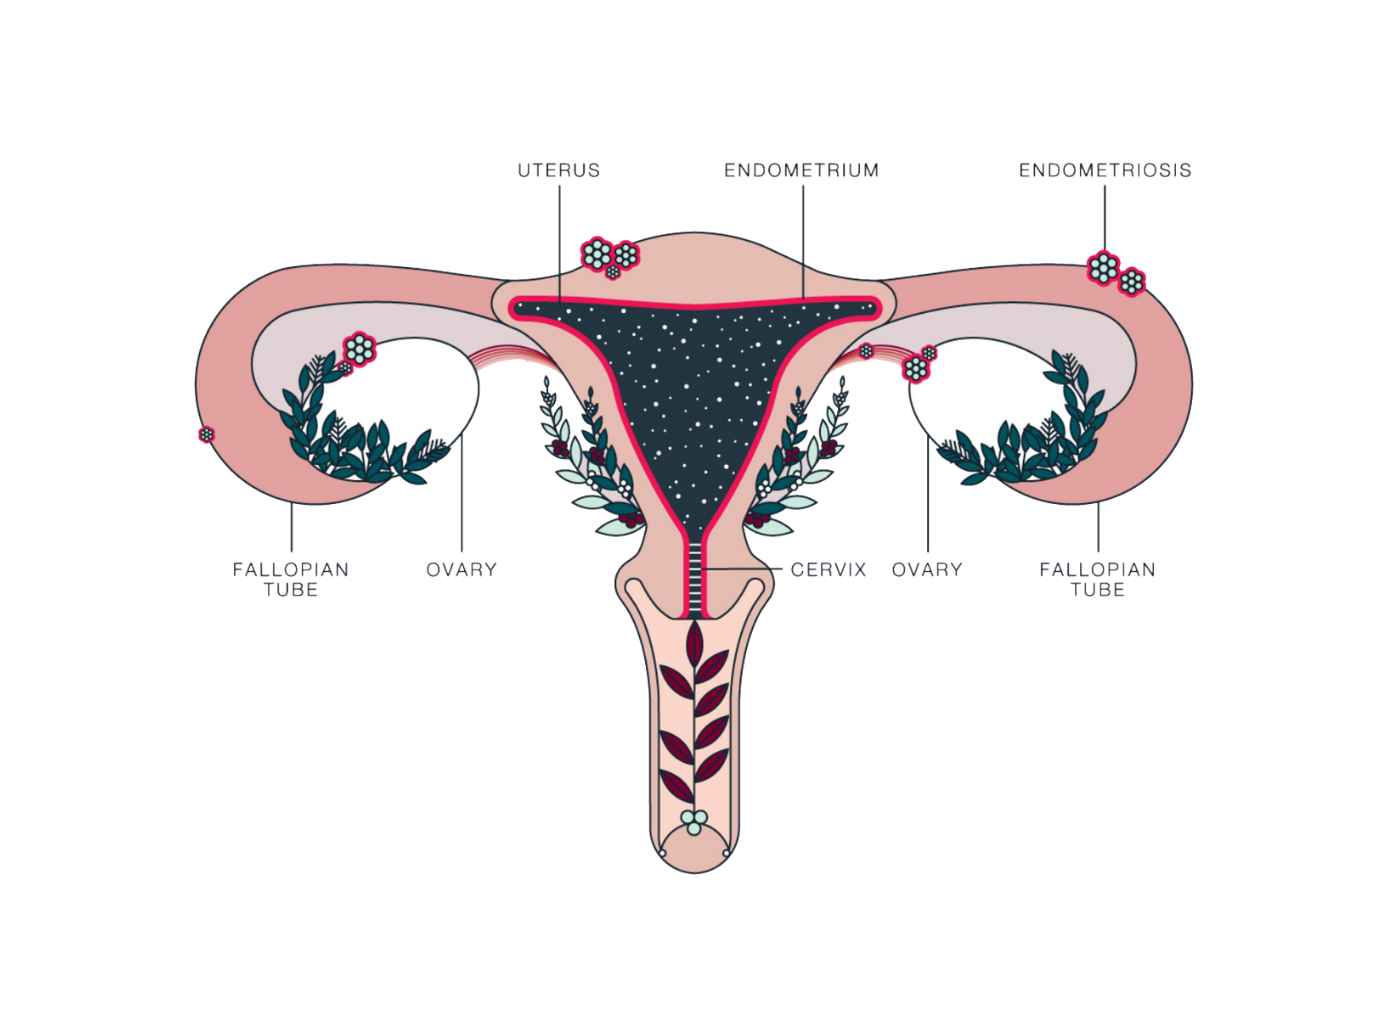

اندومتریوز؛ آندومتر بافتی است که داخل رحم را می پوشاند. اندومتریوز وضعیتی است که در آن بافتی مشابه به بافت آندومتر در خارج از قسمت رحم یافت می شود. در ناحیه لگن و شکم تحتانی (شکم) و به ندرت در سایر نواحی بدن «به دام افتاده» است. در حال حاضر مشخص نیست که چه چیزی باعث آندومتریوز می شود. عوامل متعددی وجود دارد که احتمالاً دلایل ژنتیکی، ایمونولوژیکی و هورمونی را شامل می شود.

این بیماری زمانی اتفاق میافتد که بافت مشابه با بافت داخلی رحم (آندومتر) در جایی خارج از رحم رشد میکند، معمولاً در تخمدانها، لولههای فالوپ یا سایر اندامهای لگنی. علائم آندومتریوز میتواند شامل دردهای شدید قاعدگی، درد در حین رابطه جنسی، مشکلات باروری و خونریزی غیر طبیعی باشد. با این حال، بسیاری از زنان مبتلا به آندومتریوز ممکن است بدون علائم جدی یا فقط علائم خفیف داشته باشند، که این ممکن است تشخیص بیماری را دشوار کند.

شناسایی کیستهای اندومتریوز (Endometriomas)

یکی از ویژگیهای بارز اندومتریوز ایجاد کیستهایی به نام اندومتریوما (یا "کیست شکلاتی") است که در تخمدانها یافت میشود. این کیستها از خون و بافت مشابه اندومتر تشکیل شدهاند. سونوگرافی میتواند این کیستها را به وضوح شناسایی کند. در تصاویر سونوگرافی، کیستهای اندومتریوز معمولاً به صورت تودههای گرد و یا بیضی با محتوای داخلی خاص دیده میشوند که ممکن است به رنگ تیرهتر از سایر بافتها ظاهر شوند.

اندومتریوز معمولاً به سطوح صفاقی یا سروزی اندامهای لگنی، معمولاً تخمدانها، رباطهای پهن، کولدساک خلفی و رباطهای رحمی خاجی محدود میشود.

محل های کمتر شایع شامل لوله های فالوپ، سطوح سروزی روده کوچک و بزرگ، حالب، مثانه، واژن، دهانه رحم، اسکارهای جراحی و به ندرت ریه، پلور و پریکارد می باشد.